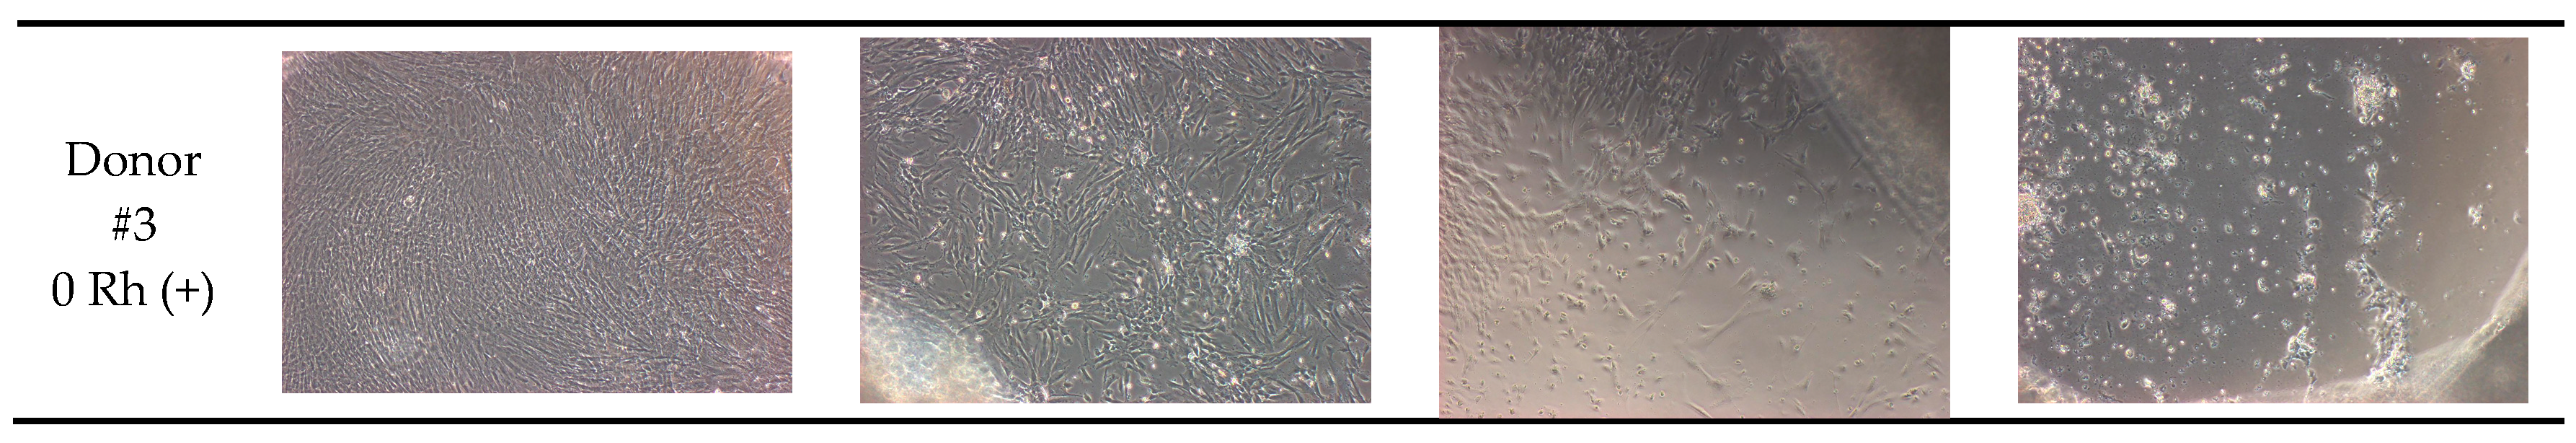

| Donor #3 | 0 Rhpositive | 95% | 75% | 60% | 30% |